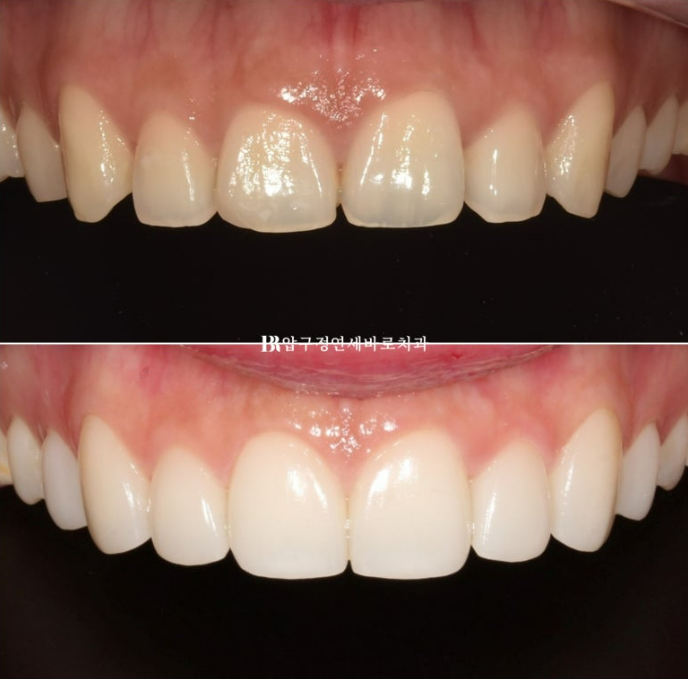

치아 사이 벌어진 공간은 라미네이트로 메꿔졌습니다.

송곳니는 기존 치아 길이를 최대한 유지하고 측절치에서 앞니로 갈수록 세로로 점점 더 길어지게 제작하여 아래로 둥근 곡선의 스마일라인을 재현합니다.

정면 비포 애프터 사진을 보면 스마일라인 변화가 좀 더 잘 보입니다.

스마일라인을 그어볼까요?

자연스러운 스마일라인은 인상을 바꿔줍니다.

아랫입술과 평행한 스마일라인

위에만 무삭제 라미네이트를 하면 아랫니와 색상 차이가 심할까봐 걱정하시는 분들이 많습니다.

환자분 본연의 치아 색에 따라 다르지만 본래 치아가 어둡지 않은 분은 아랫니에 미백치료만 해도 톤차이가 거의 없이 잘 어울러집니다.